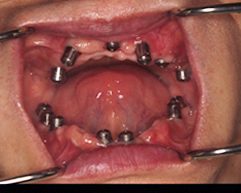

インプラント埋没後

全部の歯を抜き上下とも9本づつインプラントを埋入しました。